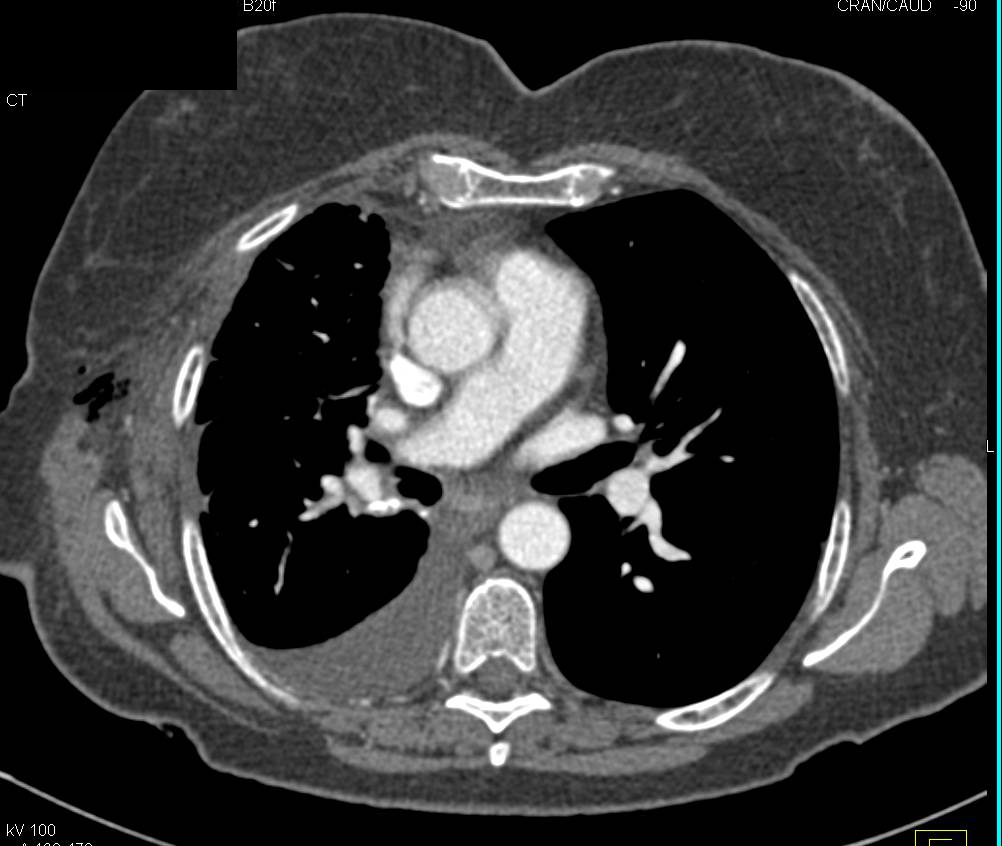

Repair of Thoracic Aorta with Endovascular Stent with Endoleaks